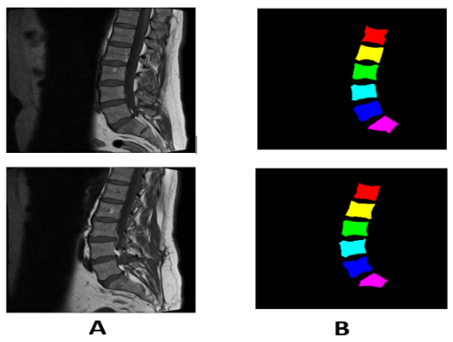

The data sets are a set of MRI images collected at Irbid Specialist Hospital in Jordan between September 2015 and July 2016 [14]. For people suffering from spinal diseases, it consists of 514 image sections of the lumbar spine, and this is after ignoring some images that were not clear due to noise [23]. Published on Mendeley Data [21]. The datasets contain 514 topics with ground truth labels, containing false color segmentation and pixel labels [1]. Ground truth labels are denoted by L1, L2, L3, L4, L5, and S [16]. All images have dimensions of 320*320. Some images of the data set are shown in Figure 2.

Figure 2. (A) Sagittal images of the spine (B) It represents ground truth images with colors